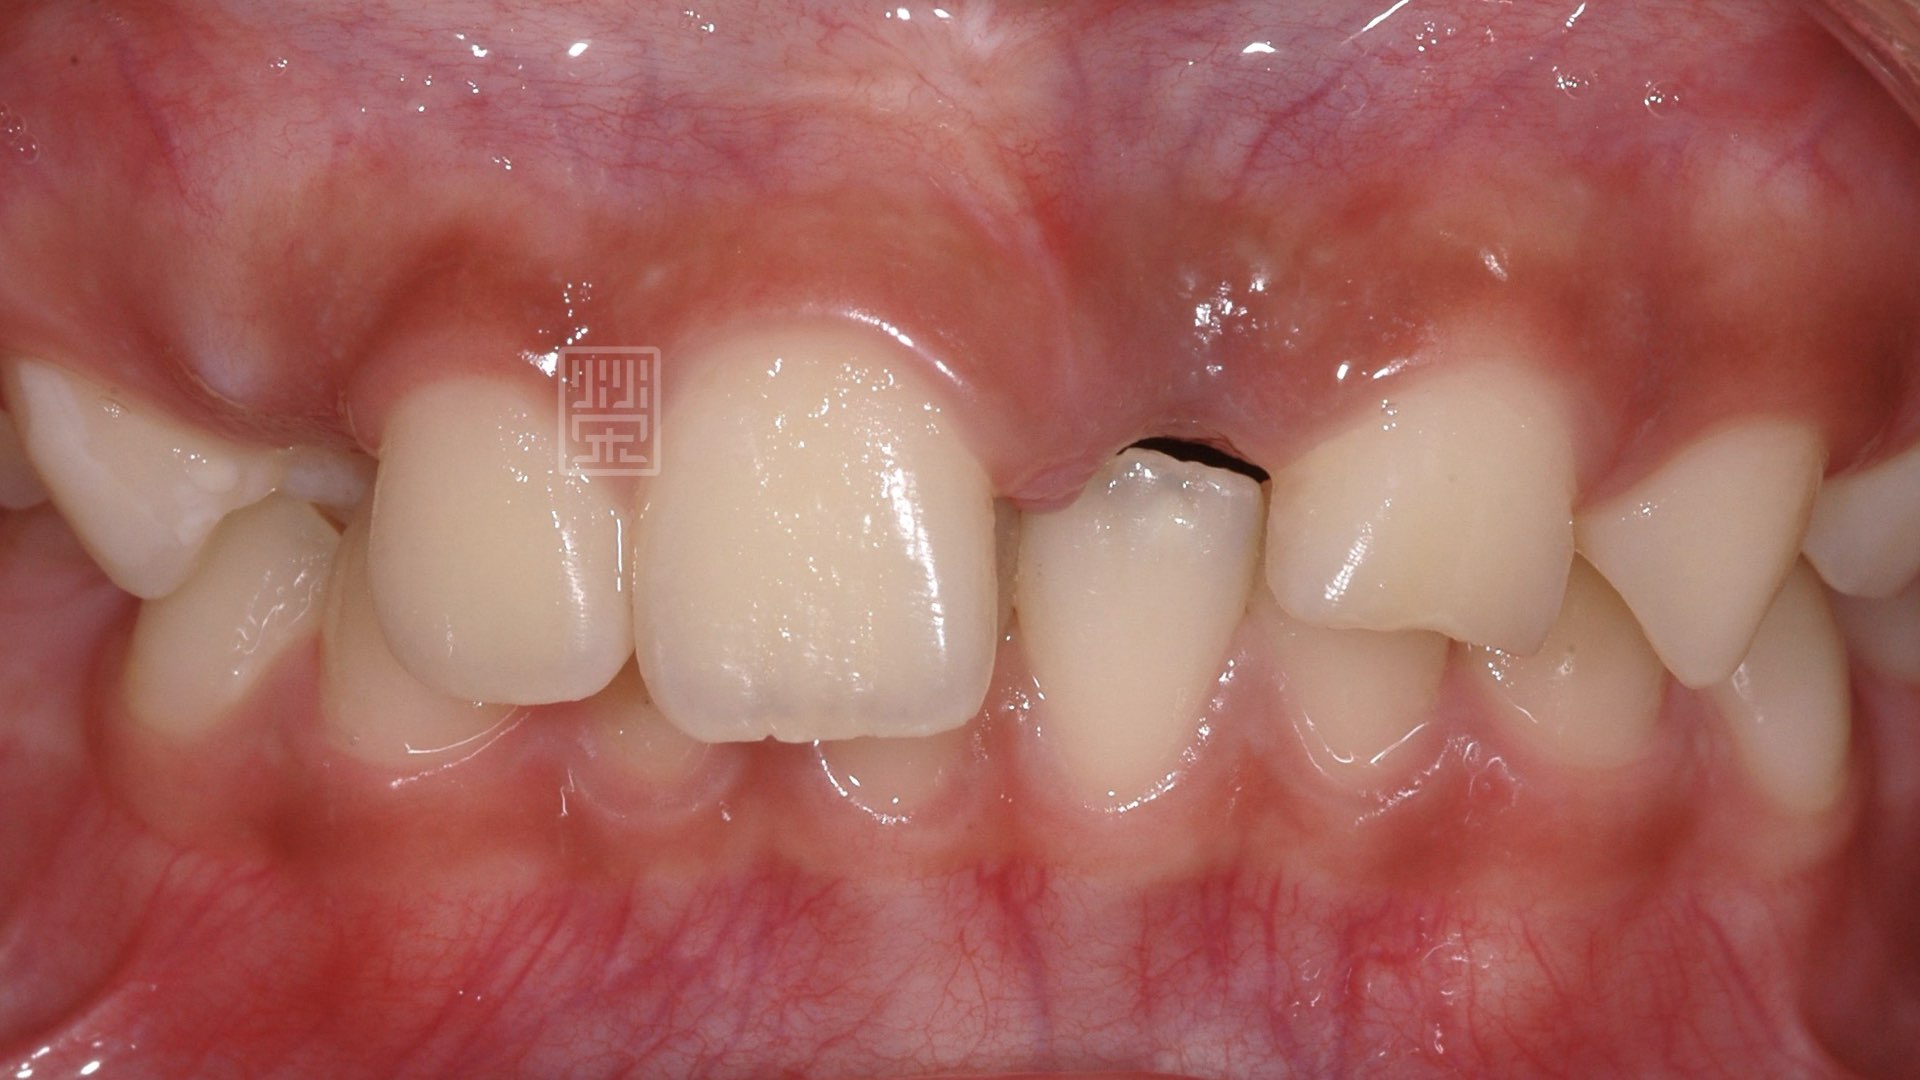

治療十二年後馬利蘭牙橋

初次補骨